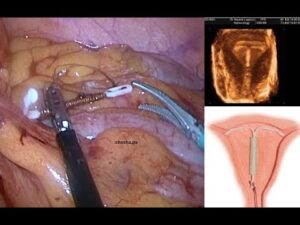

منظار للحمل

يتمكن الطبيب من التحقق من وجود الحمل عن طريق إجراء فحص البول أو الدَّم للبحث عن هرمون الحمل،

ومن ثم يجري فحص بجهاز التصوير بالموجات فوق الصوتية للتأكد من وجود كيس الحمل.

في حال تم التأكد من وجود الحمل، يقوم الطبيب بإزالة اللولب على الفور.

إذا لم يكن خيط اللولب مرئيًا ولا يمكن سحبه، فسيقوم الطبيب بإجراءات أخرى لإزالته بعد تحديد موقعه باستخدام الموجات فوق الصوتية.